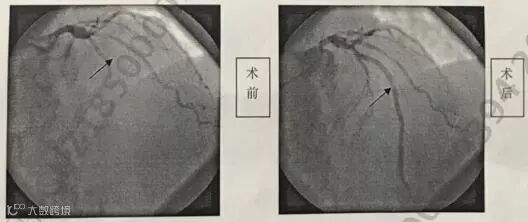

至2018年11月13日,又发作了2次,尤其第2次,早上驾车时疼痛剧烈,一旁的妻子看到后,紧急拨打了120,直接被送到江门某三甲医院急诊科,心电图示“急性前间壁心肌梗死”,同日办理了入院手续。